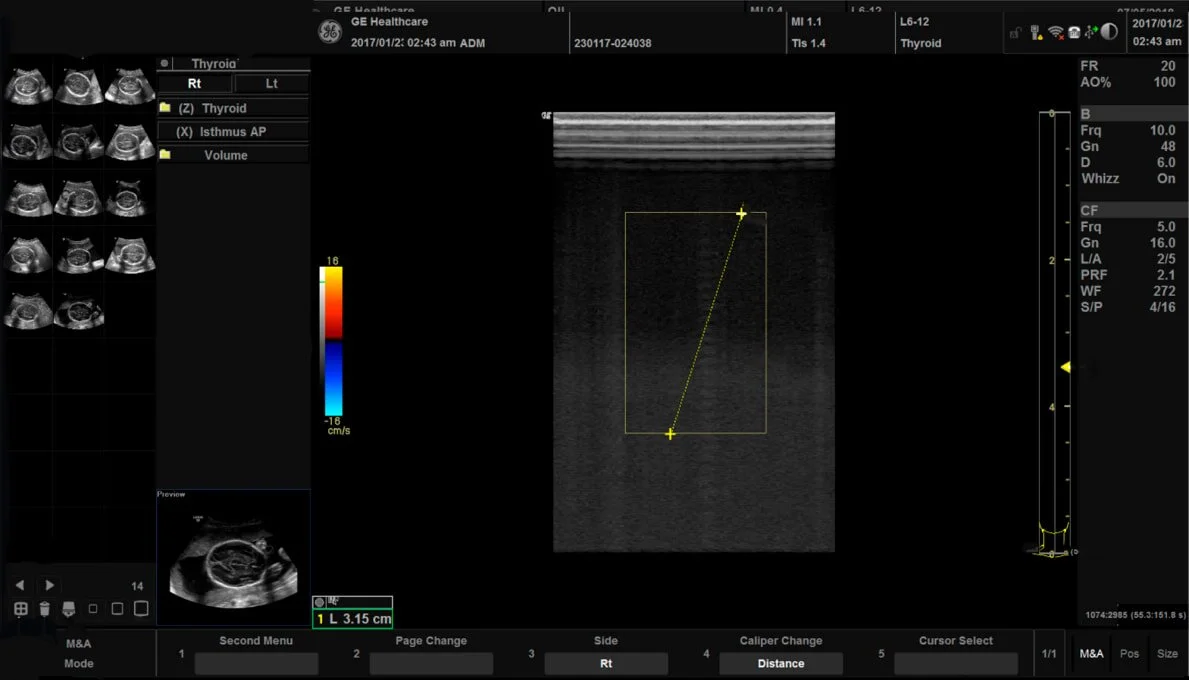

Клинические изображения

- Поверхностные органы

- L6-12-RS Линейный датчик, широкополосный, мультичастотный с диапазоном частот 4,0-13,0 МГц